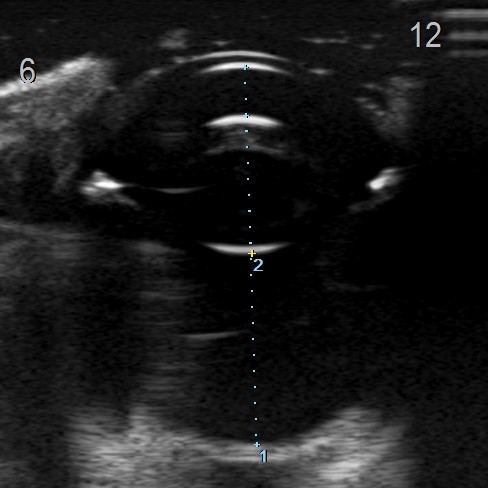

眼超音波検査

6時方向(写真左方向)に腫瘤病変がみられた

超音波拡大部

腫瘤病変がみられ、眼内からくる腫瘤病変はないことを確認